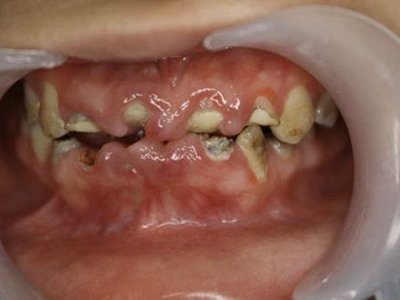

肿块有的有蒂,如息肉状;有的无蒂,基底宽广,生长较慢,但在女性妊娠期间可能迅速增大。较大的肿块可以遮盖一部分牙及牙槽突,表面可见牙压痕,易被咬伤而发生溃疡,伴发感染。随着肿块的增长,牙槽骨壁逐渐被破坏,牙可能发生松动、移位。

局部刺激因素,包括菌斑、牙石、食物嵌塞或不良修复体的刺激,引起局部长期慢性炎症,致使牙龈结缔组织形成反应性增生物,即牙龈瘤。此外,牙龈瘤可能和内分泌有关,妇女怀孕期间容易发生牙龈瘤,而分娩后会缩小或停止生长。